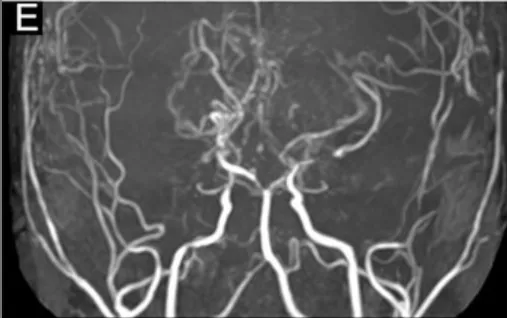

复查发现,他的大脑后动脉(负责给枕叶、顶叶供血,这两个区域管视力和肢体感觉)狭窄加重了——原来,第一次手术解决了前循环的供血问题,但烟雾病是进展性疾病,后循环的血管还在慢慢变窄,之前的搭桥血管已经“供不上”了,大脑再次陷入缺血。

2年后的MRA和DSA显示进行性PCA狭窄(图E)